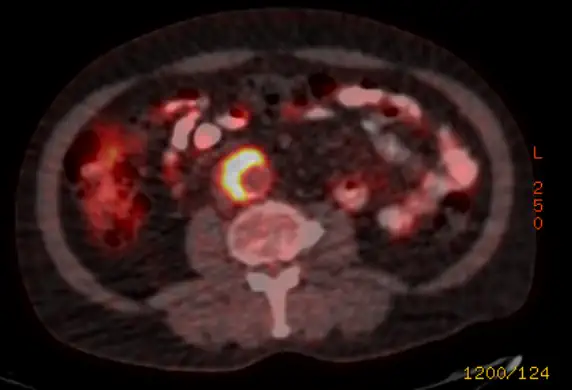

Local obstruction, on the other hand, results from other causes. First, it can be a result of atherosclerosis. Less commonly, acute limb ischemia can result from complications of systemic disease such as vasculitis or arterial dissection in FMD. Finally, it can be a complication of treatment. Acute limb ischemia can result from stent or graft failure. It can result from a complication of a closure device such as Angio-seal™: